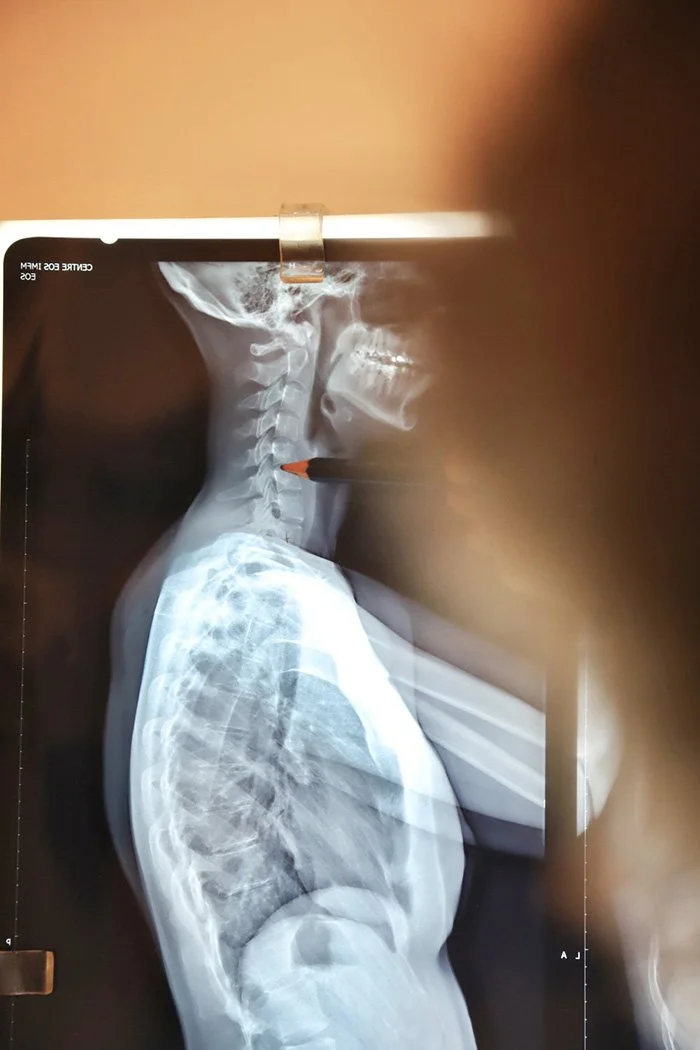

L’analyse Gonstead

La technique Gonstead permet d’effectuer une analyse approfondie de votre colonne vertébrale en utilisant 5 critères pour détecter la présence de subluxation vertébrale.